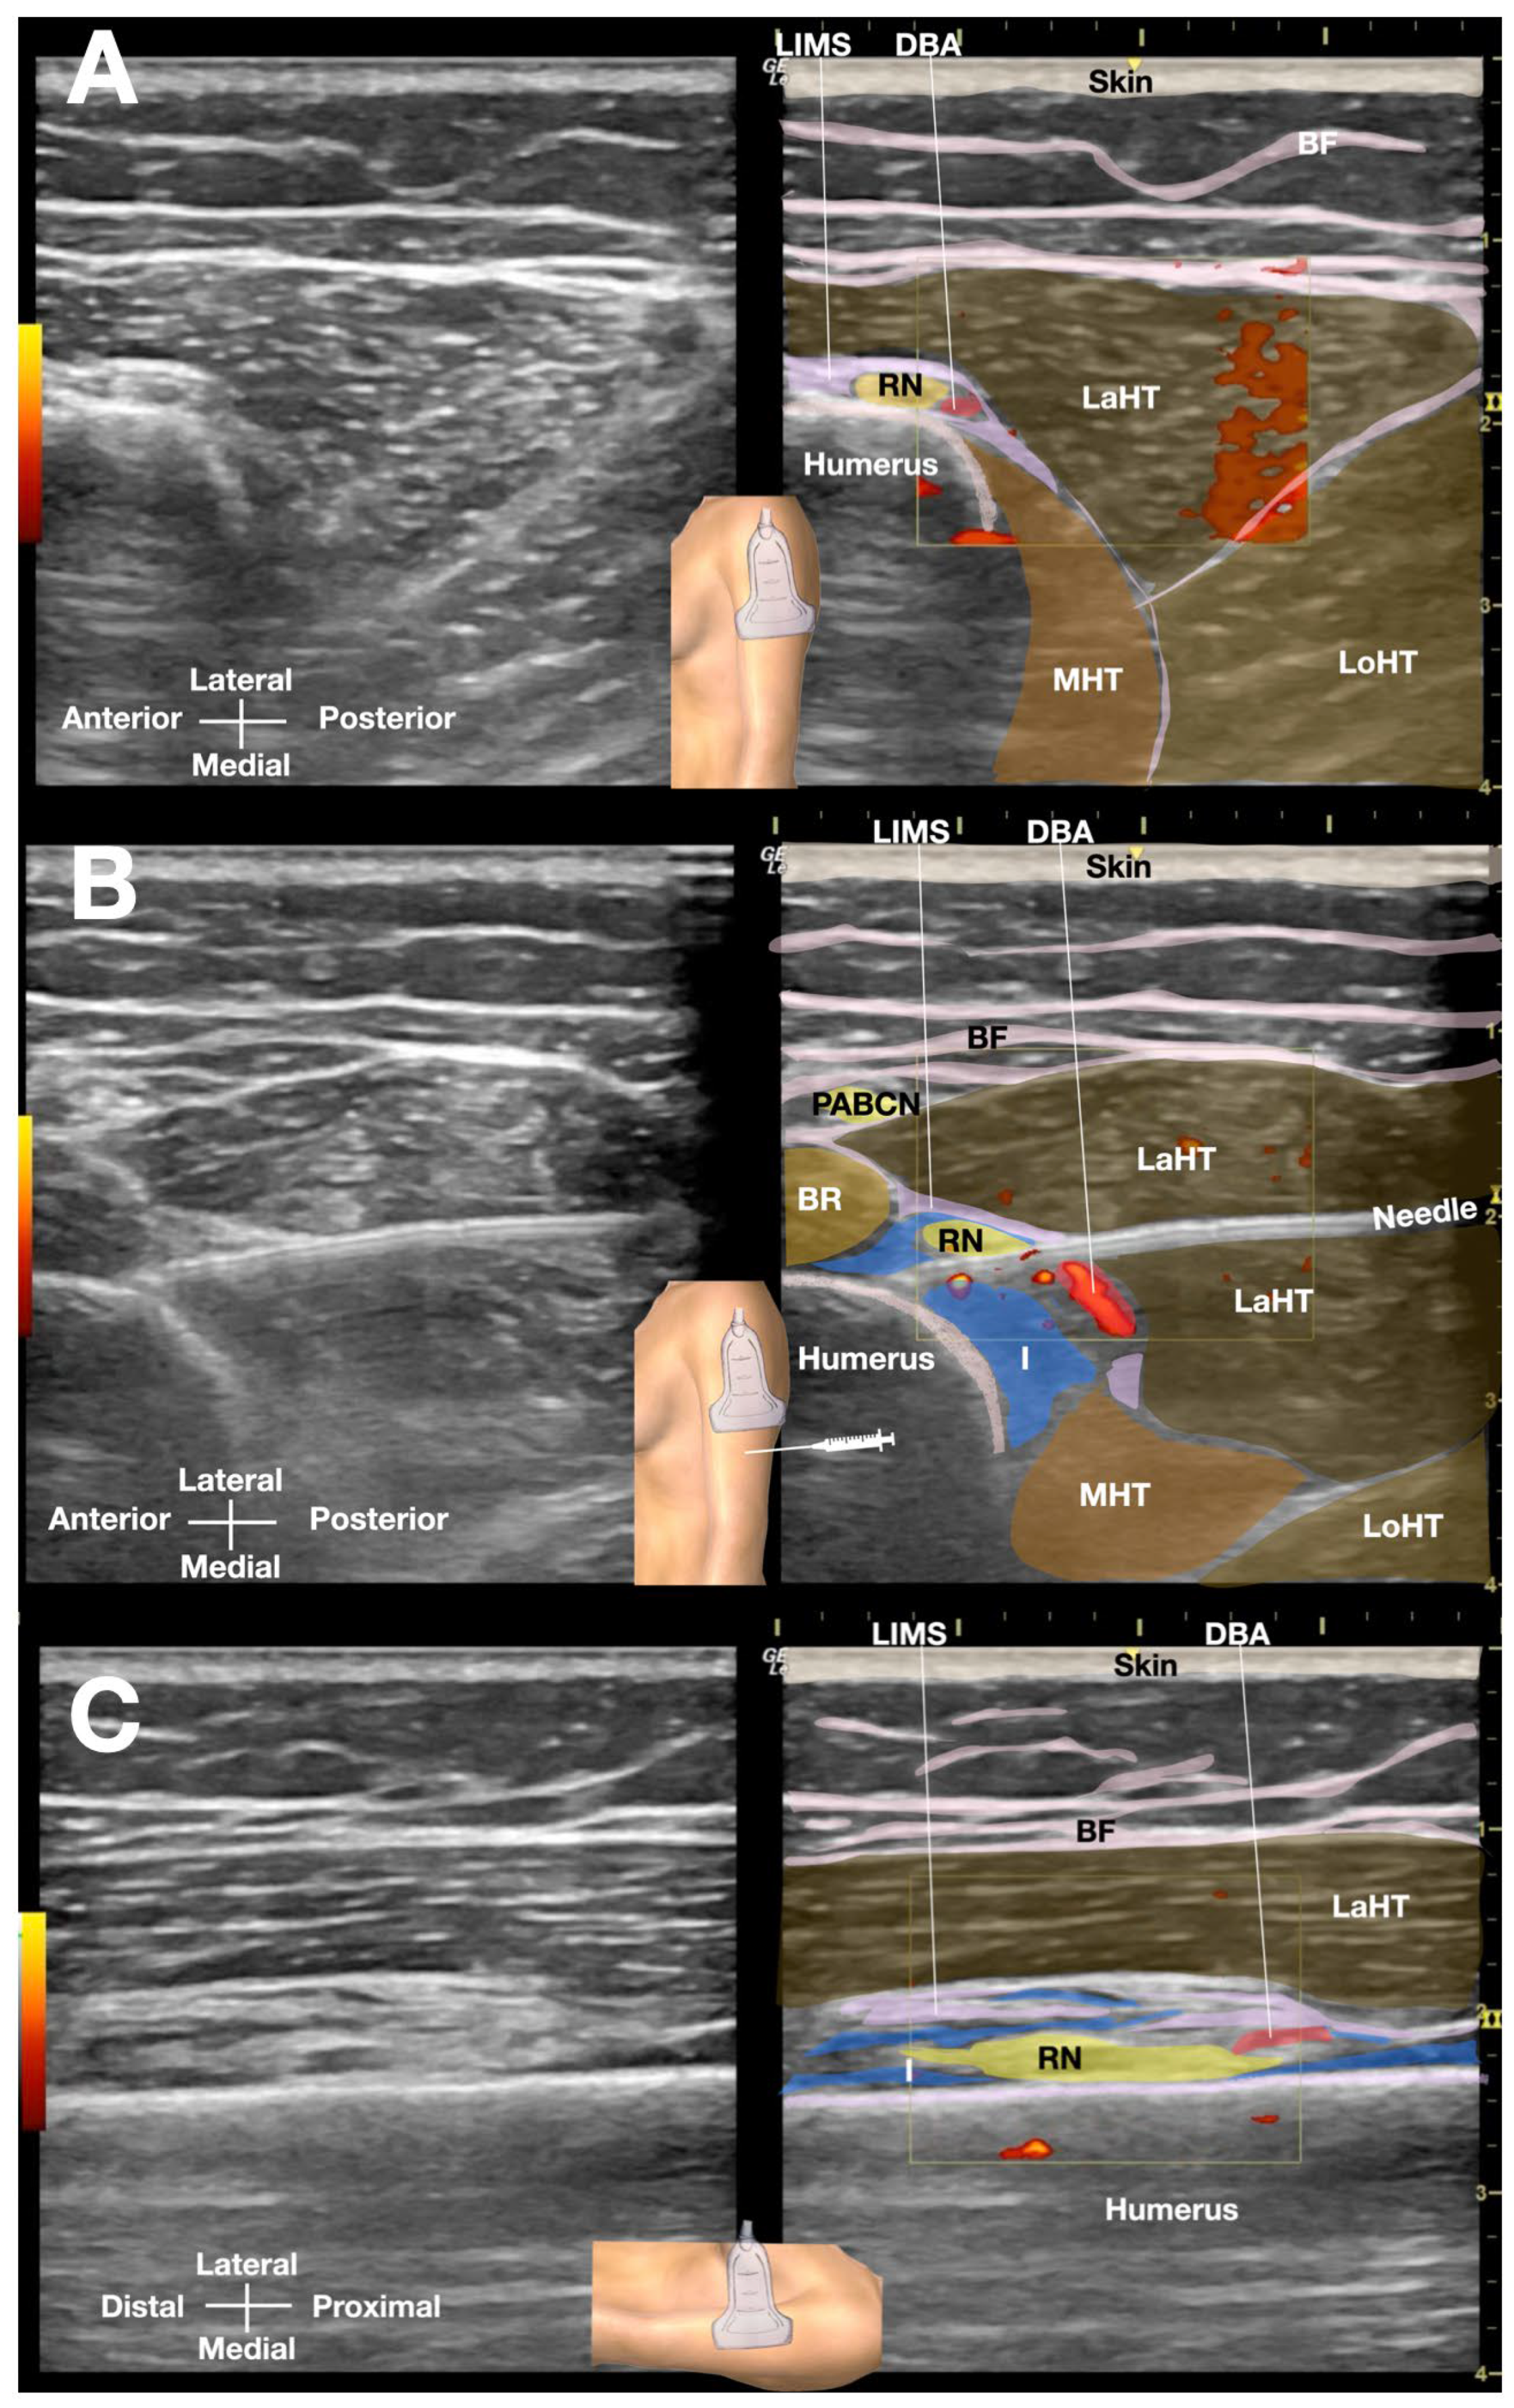

The patient was positioned side-lying for the procedure, targeting the proximal spiral groove using a posterior-to-anterior in-plane needle approach. After numbing the skin with 1% lidocaine, a total of 50 mL of D5W with no LA was injected under real-time sonographic guidance to hydrodissect the radial nerve the spiral groove (Figure 3 or Video 2). Immediate post-procedural assessment revealed marked improvement in wrist extension, indicating a positive therapeutic response (Figure 4 and Video 3).

Figure 3. Ultrasound-guided hydrodissection of the radial nerve at the spiral groove. A) Short-axis view showing the pre-hydrodissection sonoanatomy of the radial nerve in the spiral groove, visualizing the radial nerve adjacent to the humeral cortex and within the lateral intermuscular septum. B) Post-hydrodissection appearance of the radial nerve, completely separated from the humerus, lateral intermuscular septum, and lateral head of the triceps by the injectate (5% dextrose in water without local anesthetics). C) Long-axis view of the radial nerve in the spiral groove post-hydrodissection, with the injectate separating the nerve from the bony cortex of the humerus and the surrounding soft tissues. BF: brachial fascia; DBA: deep brachial artery; I: injectate; LaHT: lateral head of triceps; LIMS: lateral intermuscular septum; LoHT: long head of triceps; MHT, medial head of triceps; RN: radial nerve. <<<Video 2>>> https://www.dropbox.com/scl/fi/enkxlodfwzr6i1qahzv22/Radial-Nerve-Palsy-HD_Labeled_new.mp4?rlkey=ciuyx7ci8rnpfahthtf42mf9w&dl=0. Video 2 Title: Ultrasound-Guided Hydrodissection of the Radial Nerve at the Spiral Groove. Video 2 Legend: This video illustrates the ultrasound-guided hydrodissection of the radial nerve at the spiral groove. The ultrasound transducer is positioned in a short-axis view to the humerus, using an in-plane needle approach from posterior to anterior to visualize the radial nerve adjacent to the humeral cortex. A 5% dextrose in water without local anesthetic was used to hydrodissect the radial nerve, completely separating it from the humerus, lateral intermuscular septum, and lateral head of triceps. The still images captured from the video are clearly labeled. Key anatomical structures include BF: brachial fascia; DBA: deep brachial artery; I: injectate; LaHT: lateral head of triceps; LIMS: lateral intermuscular septum; LoHT: long head of triceps; MHT, medial head of triceps; RN: radial nerve.